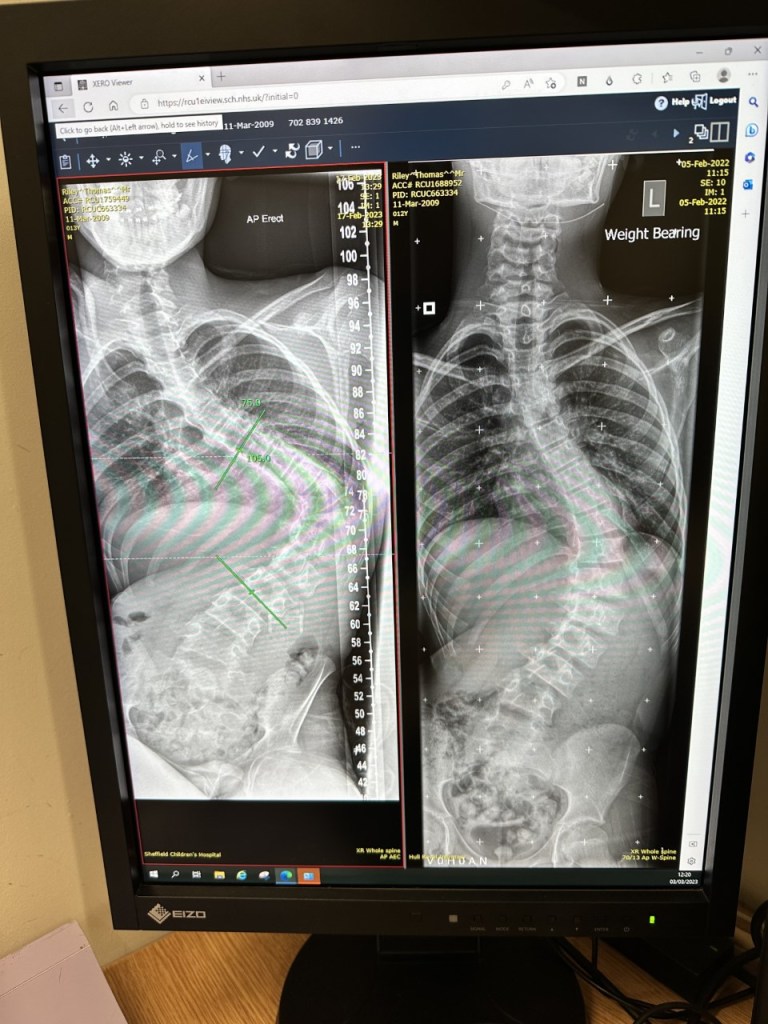

We have also had another appointment with T’s spinal surgeon in Sheffield. We knew T’s Scoliosis had deteriorated. However, we weren’t quite prepared to see this:

The image on the right shows T’s spine in February 2022, the image on the left shows his spine now. His curvature is now over 100, and the Dr feels surgery is the best option for him. As T’s muscles are weakening, if his spine is not straightened, he will effectively become a ‘one armed man’, as he will continually have to use his left arm to stop himself from falling over/out of his chair. T’s stomach is definitely compressed, hence the lack of appetite, but thankfully his lungs and heart seem to be OK at present. That would, however, change if we leave his spine untreated.

The operation itself will last most of the day, with T going down at approximately 8.30am and returning at around 4.30pm. As he is young and his spine is still reasonably flexible, the Dr is confident that the ‘straightening’ aspect of the surgery will happen more or less of its own accord, and then it will be a case of fixing it in place. All sounds relatively straight forward! However. And sadly, it is a big ‘however’. When this surgery is performed, something called ‘Spinal Tracing’ is used, which is basically electrical currents which run through the spinal cord throughout the surgery. If there are any issues with the cord, the tracing picks this up and alerts the surgical team who then make adjustments to try to prevent any damage. Due to T’s Friedreichs Ataxia, his nerve conduction does not work correctly, meaning that it is an almost certainty that the spinal tracing will not work. The Dr was incredibly honest (one of the reasons we like him so much), and stated that if this were an able bodied person, and the tracing did not work, he would refuse to perform the surgery due to the increased level of risk. He described it as ‘operating blind’. However, he has performed this surgery successfully on a number of FA patients.

The odds of a serious complication in a surgery such as this are approximately 1-2%, but the ‘serious complication’ in question could be paralysis from the waist down and loss of bowel, bladder and sexual function.